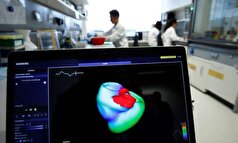

- مطالعه: هوش مصنوعی، الکتروکاردیوگرامهای استاندارد را قادر میسازد تا نقصهای ساختاری را تشخیص دهند

- دانشمندان روسی روشی برای تشخیص حملات قلبی در مراحل اولیه ابداع کردهاند